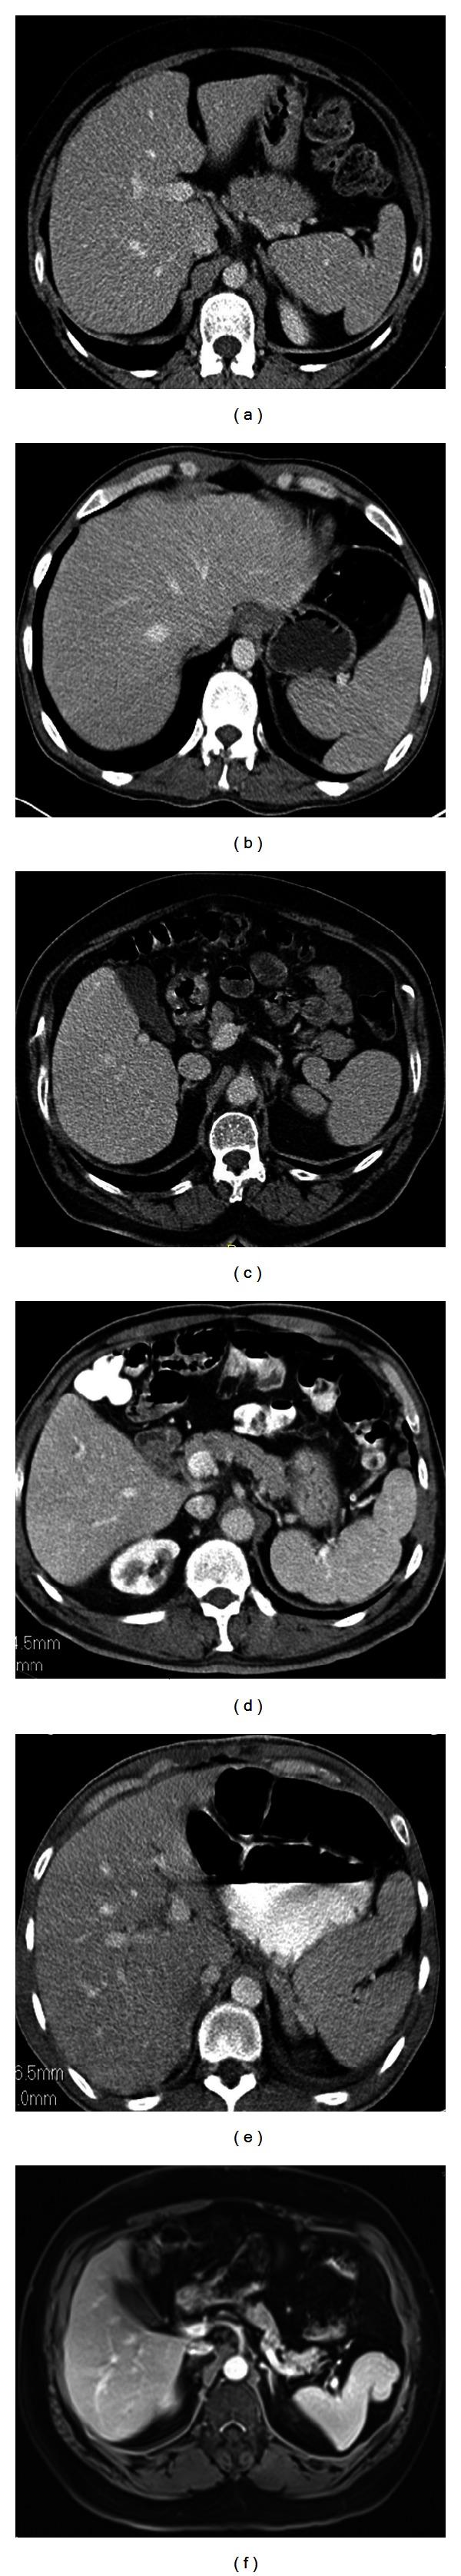

脾脏在形状、大小和位置上的异常:图文综述

Splenic anomalies of shape, size, and location: pictorial essay.

Spleen can have a wide range of anomalies including its shape, location, number, and size. Although most of these anomalies are congenital, there are also acquired types. Congenital anomalies affecting the shape of spleen are lobulations, notches, and clefts; the fusion and location anomalies of spleen are accessory spleen, splenopancreatic fusion, and wandering spleen; polysplenia can be associated with a syndrome. Splenosis and small spleen are acquired anomalies which are caused by trauma and sickle cell disease, respectively. These anomalies can be detected easily by using different imaging modalities including ultrasonography, computed tomography, magnetic resonance imaging, and also Tc-99m scintigraphy. In this pictorial essay, we review the imaging findings of these anomalies which can cause diagnostic pitfalls and be interpreted as pathologic processes.

摘要

脾脏可出现多种异常,包括其形状、位置、数量和大小。虽然这些异常大多是先天性的,但也有后天性类型。影响脾脏形状的先天性异常有分叶、切迹和裂隙;脾脏的融合和位置异常有副脾、脾胰融合和游走脾;多脾可与一种综合征相关。脾组织植入和小脾脏是分别由创伤和镰状细胞病引起的后天性异常。通过使用不同的成像方式,包括超声、计算机断层扫描、磁共振成像以及锝-99m闪烁扫描,这些异常很容易被检测到。在这篇图文文章中,我们回顾了这些异常的影像学表现,它们可能导致诊断陷阱,并被解释为病理过程。